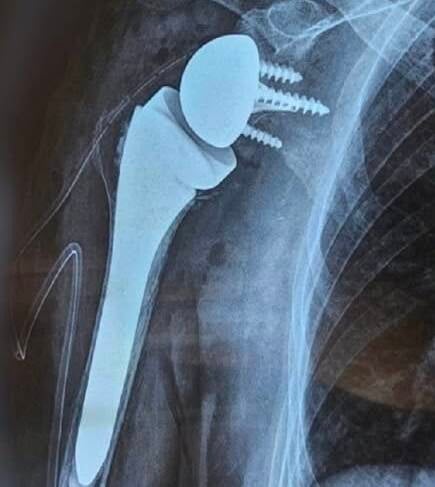

Pose d’une prothèse d’épaule (inversée) chez une patiente de 75 ans souffrant d’omarthrose sévère, impactant fortement sa qualité de vie au quotidien.

Ci-dessous, les radiographies prises avant et après l’intervention.